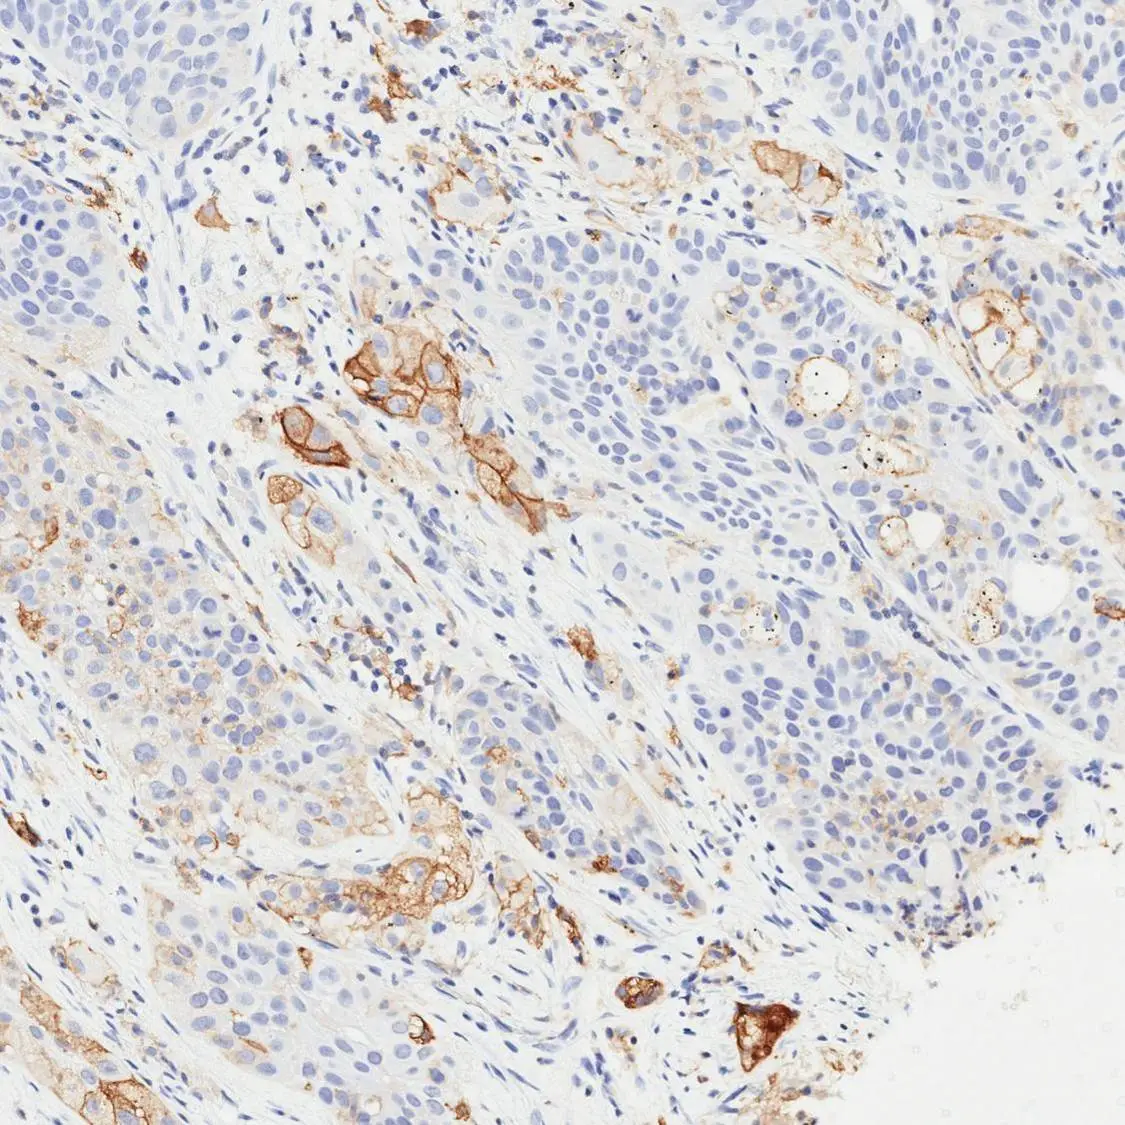

Anti-PD-L1 antibody [H302] HistoMAX™ used in IHC (Paraffin sections) (IHC-P). GTX639925

GTX639925 IHC-P Image

Optimal staining result of the human TNBC, tissue core no. 7, following the vendor recommended protocol settings.

No staining reaction is observed. The tumour was categorized as CPS Low (<10).